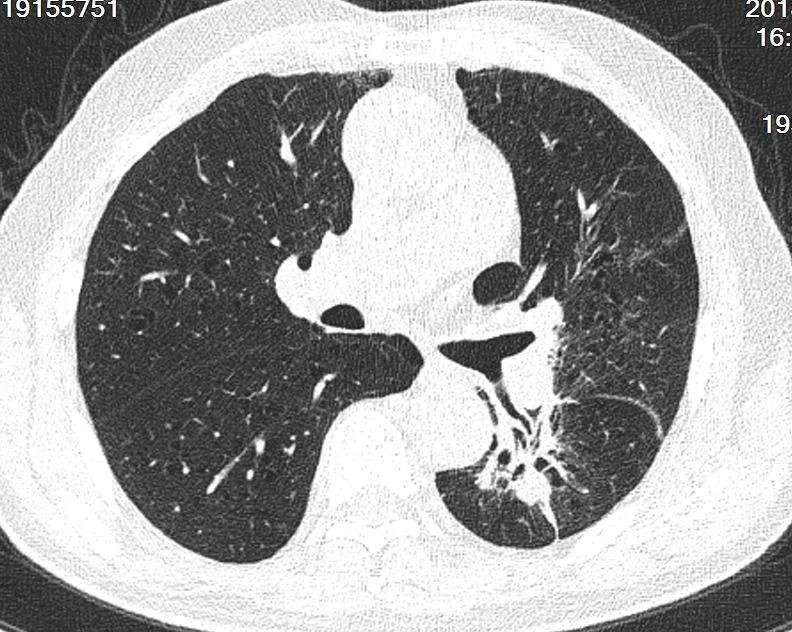

术后第二天胸部CT提示左肺门占位,左上肺不张,左肺门粒子植入术后

当复诊检查结果出来时,周大爷和江爱桂博士都显得异常激动,因为患者的支气管明显开通,左上肺复张,左肺实体病灶缩小50%。

术后联合化疗两月后复查胸部CT提示支气管明显开通,左上肺复张,左肺实体病灶缩小50%